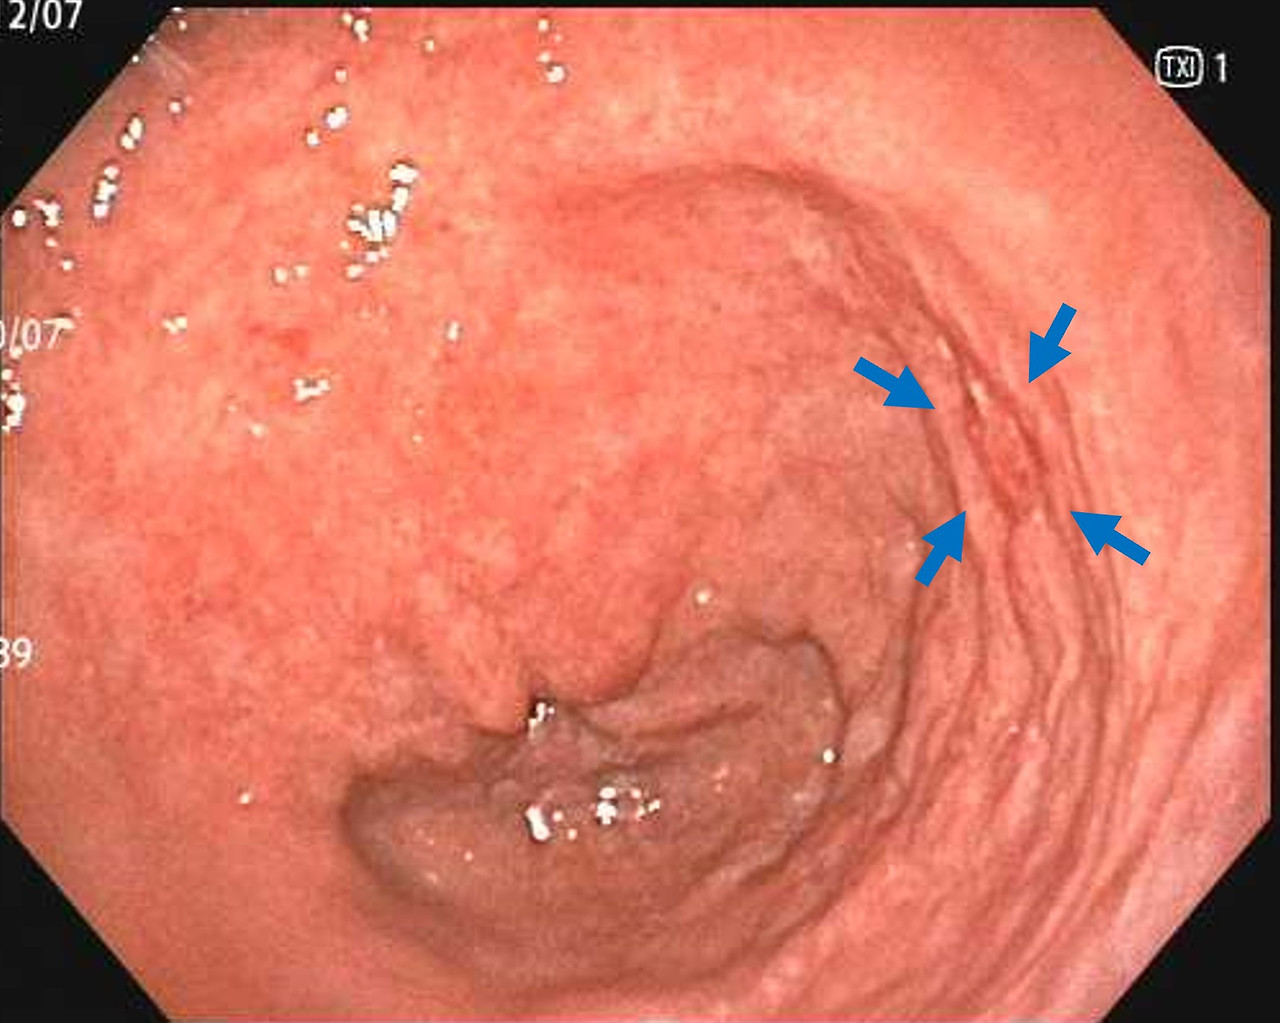

- 미란, 궤양, 백태성 변화 등이 관찰되는 경우

미란·궤양의 변성 여부 평가

겉으로 보기에는 단순 궤양이지만 실제로는 악성 궤양의 형태인 경우가 있어, 의심 부위에서는 조직검사가 필수입니다. 특히 경계가 불규칙하거나 두꺼워 보이는 궤양은 초기 암일 가능성을 배제하기 위해 반드시 세포 검사가 이루어져야 합니다.